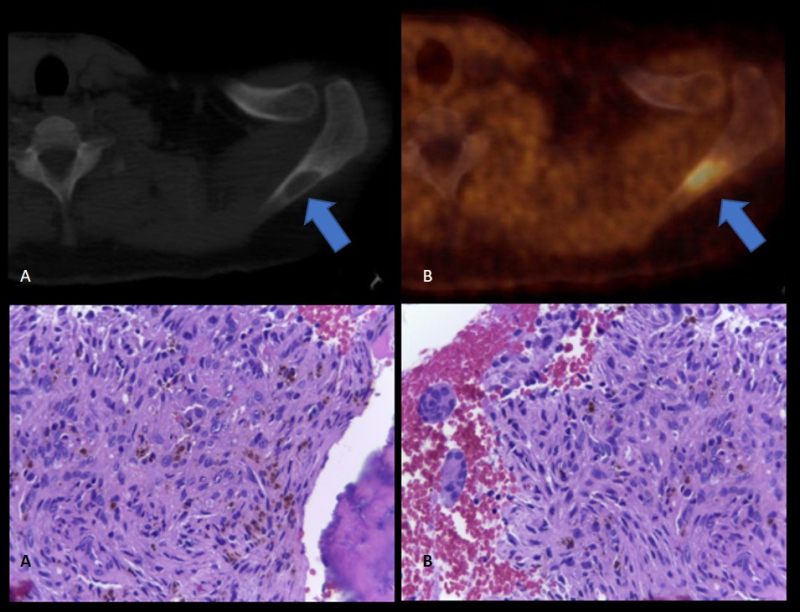

Paciente de 72 años con insuficiencia renal crónica en plan de trasplante, con cirugía previa de paratiroides. Por valores elevados persistentes de PTH y ante resultados confusos del centellograma con 99m Tc- sestamibi, se realiza PET-CT con 18F-Colina para detectar presencia de tejido paratiroideo hiperfuncionante. En el estudio híbrido morfo-molecular se evidencia imagen nodular de 17 mm en región ínfero medial cervical anterior con aumento de la captación del radiotrazador (SUV máx. 3,5) consistente con tejido paratiroideo (fig. 3). Además, se detecta una lesión predominantemente lítica e hipercaptante de 26 mm de diámetro en la espina del omóplato izquierdo, que cursaba en forma asintomática (fig. 4, arriba). Se realiza biopsia de la misma, dando como resultado tumor pardo (fig. 4, abajo).